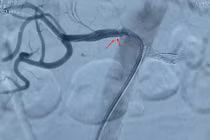

Viên nén Hurmat 25mg bị thu hồi toàn quốc do không đạt tiêu chuẩn chất lượng về chỉ tiêu định tính Captopril Disulfid.

Viên nén Hurmat 25mg bị thu hồi toàn quốc do không đạt tiêu chuẩn chất lượng về chỉ tiêu định tính Captopril Disulfid/ Ảnh stp.bacninh.gov.vn